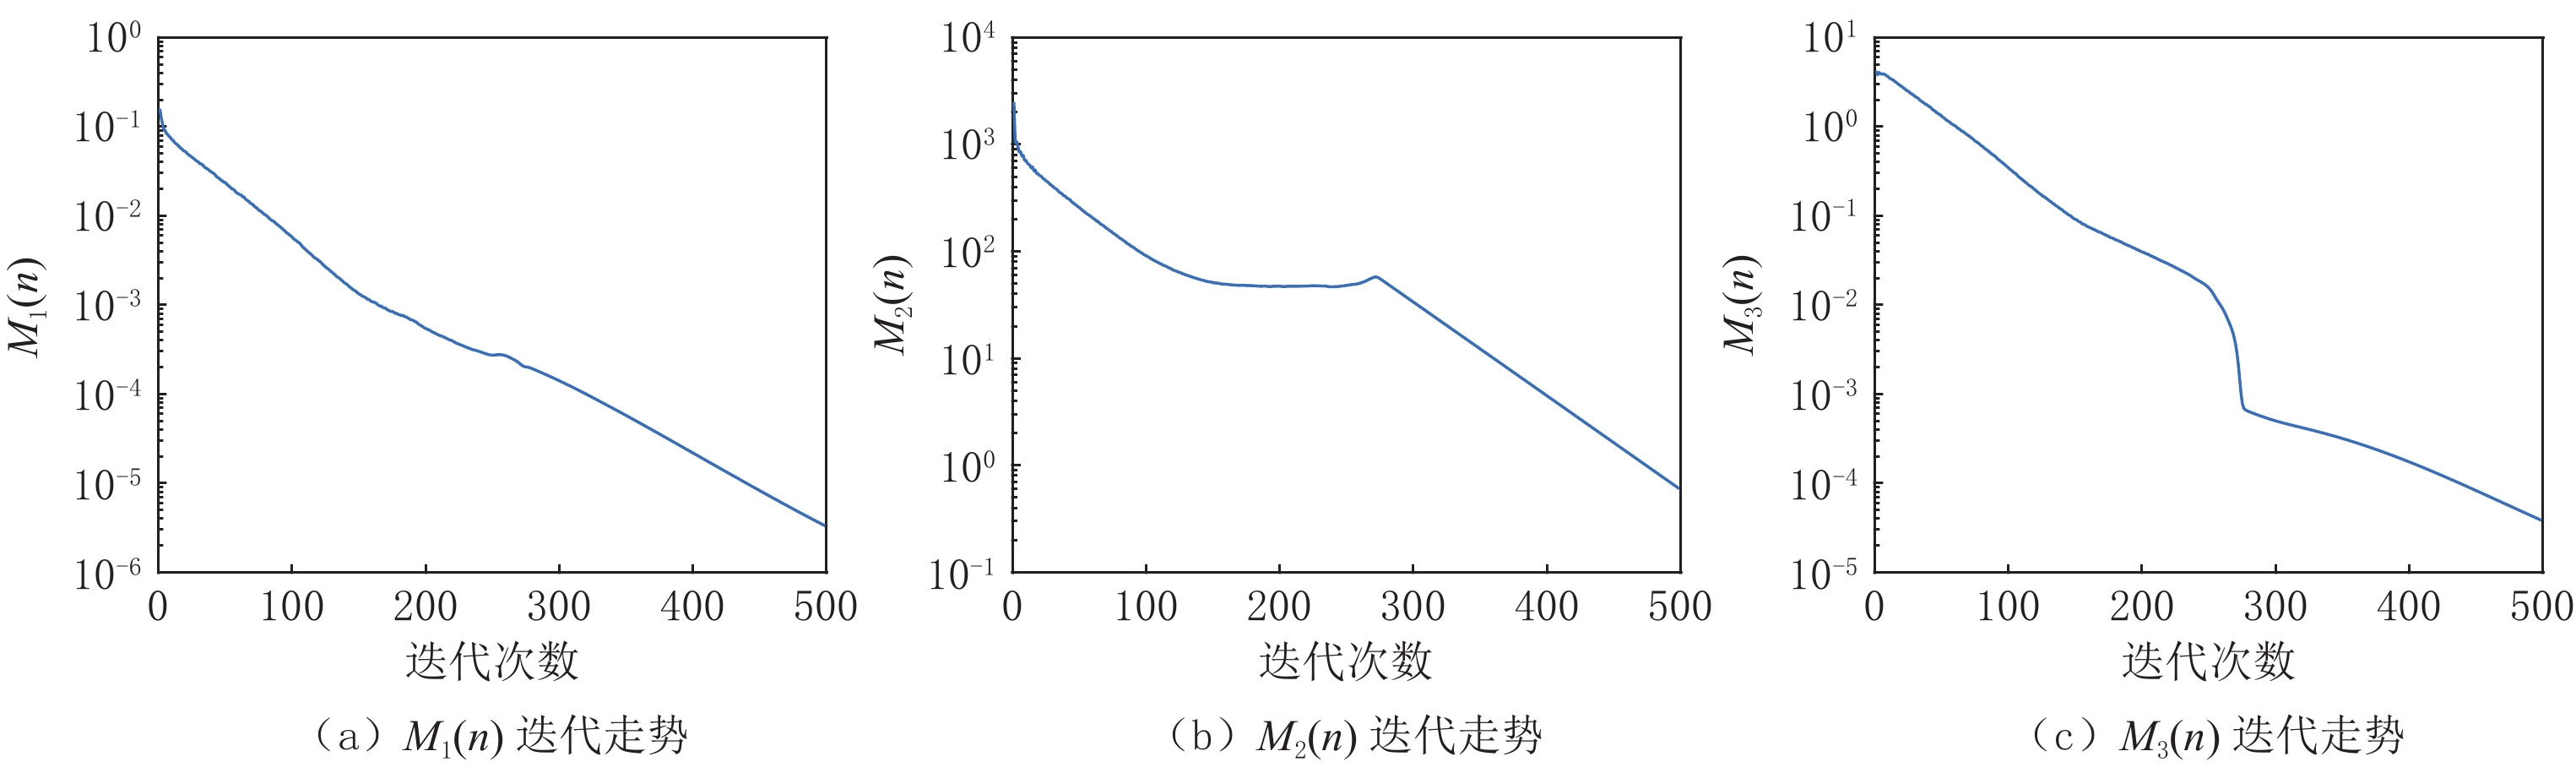

对于算法收敛性的评估,引入以下3个度量标准,通过观察这3个度量标准来判断算法的收敛性:

$$ {{{{M}}_1}\left( n \right) = {\rm{RMSE}}\Big( {{{\boldsymbol{f}}_n},{{\boldsymbol{f}}_{{\rm{truth}}}}} \Big)} \text{,} $$ (18) $$ {{M_2}\left( n \right) = \big\| {{\boldsymbol{g}} - {\boldsymbol{A}}{{\boldsymbol{f}}_n}} \big\|} _2\text{,} $$ (19) $$ {{M_3}\left( n \right) = \frac{{{{\big\| {{{\boldsymbol{f}}_n}} \big\|}_{{\rm{TV}}}} - {{\big\| {{{\boldsymbol{f}}_{{\rm{truth}}}}} \big\|}_{\rm{TV}}}}}{{{{\big\| {{{\boldsymbol{f}}_{{\rm{truth}}}}} \big\|}_{{\rm{TV}}}}}}} \text{,} $$ (20) 其中(18)式代表重建图像与真实图像间的均方根误差;(19)式代表重建图像的投影与真实投影间的差异,(20)式代表重建图像的TV值与真实图像TV值之间的相对误差。

在此实验的研究中,投影数据是充分且准确的,所以在重建图像达到收敛时,这些度量标准要达到充分小,表示该算法在高精度重建的同时达到了收敛。如图4和图5所示,其分别展示了在重建Shepp-Logan和FORBILD模体时RTV最小化重建算法的收敛行为,其中图(a)~图(c)图分别展示了(18)~(20)式所示的度量标准的迭代走势。

图4和图5中的(a)图显示的是图像误差的迭代走势。而在重建这两个模体时,其

${M_1}\left( n \right)$ 分别迭代到200多次和300多次时达到了10-4,在迭代到500次时分别达到了10-5和10-7,如果继续迭代,其${M_1}\left( n \right)$ 还会有继续下降的趋势;(b)图显示了数据误差的迭代走势,从图中可以看出数据误差在不断减小,但是在重建过程中有一个向上的抖动,这种现象是TV类算法在迭代过程的一个特点,在迭代过程中经常出现,并不会影响该算法的收敛性,振动之后,其相对误差会继续减小,这说明优化模型的解仍然趋向收敛;(c)图显示了TV值的相对误差,从图中可见其整体下降趋势,并且在迭代到500次之后都还有继续下降的趋势。总之,无论是从(a)图,还是(b)图、(c)图来看,重建结果都已在有限次的迭代次数下使误差达到了充分小,并且还有继续下降的趋势,直至达到其收敛态。